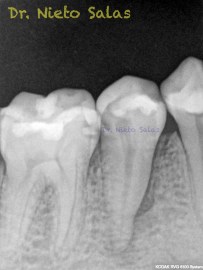

Y este sería el otro caso:

Es muy importante cambiar la proyección de las Rx para tener más información de como hemos sellado el sistema de conductos.